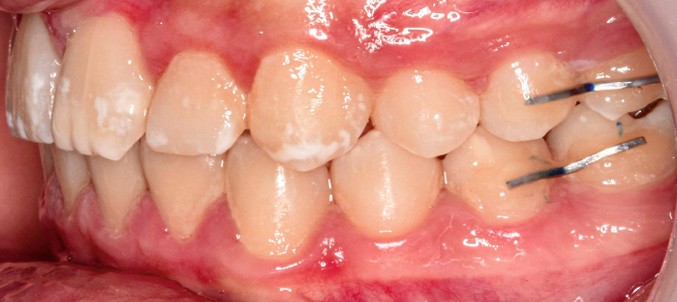

Sur le plan alvéolo-dentaire (fig. 1b) :

- Classe II subdivision gauche avec déviation du point inter-incisif mandibulaire à gauche ;

- occlusion inversée entre 22 et 32 ;

- dysharmonie dento-arcade (DDA) sévère ;

- 13 en position haute retenue.